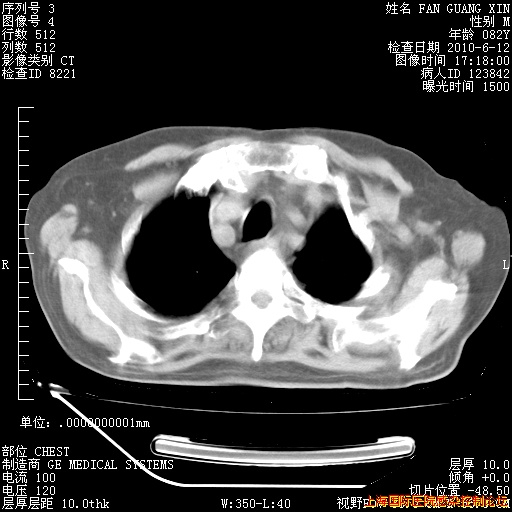

6月12日纵膈窗

整整相隔30天的肺部CT好像有所好转啊。甲强龙减量第3天,需要观察体温。

海管,自昨日你和我通完话后,不知您岳父消化道症状有无缓解?体温怎样?阅读7.12日胸部ct,个人认为目前激素治疗是有效的,甲强龙减量是适宜的。因在抗痨治疗,需密切观察肝功、肾功能和血常规。不过,老年、长期住院和大量使用激素,很担心菌群失调发生